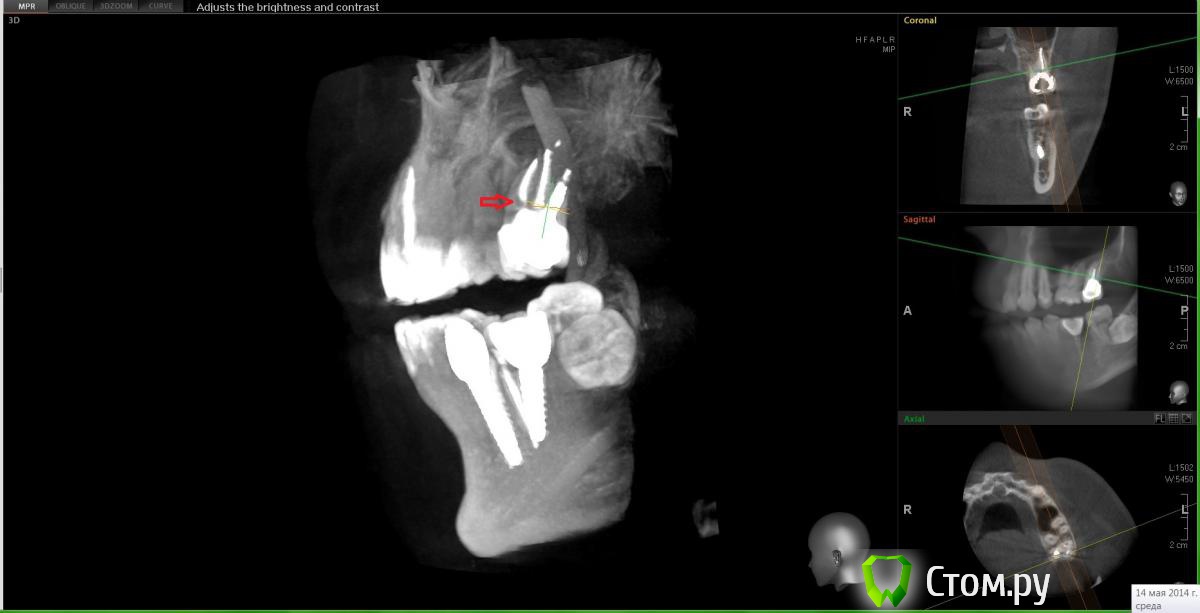

Еще один прицельный снимок этого зуба. Есть вариант того, что там пропущен канал?[/url]

Сначала предположила что есть пропущенный канал исходя из этого:

Но оказалось, что это как бы "пора"